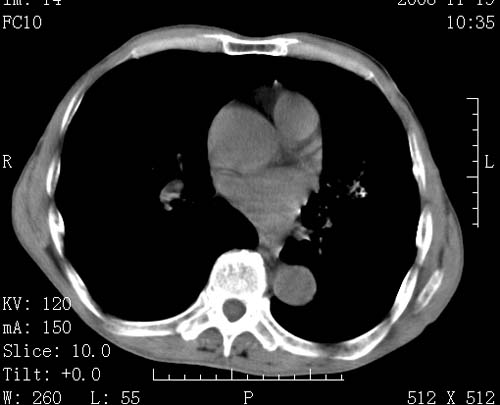

标题: CT16691:m 67 胃镜确诊食管下段及贲门癌 [打印本页]

标题: CT16691:m 67 胃镜确诊食管下段及贲门癌

术前查体,双肺部结节是转移?结核?请点评

转移 隆突下淋巴结亦肿大

首先考虑转移,纵隔内淋巴结亦肿大;

1)符合食管癌表现。2)两肺及纵隔淋巴结多发性转移瘤。3)左肺上叶舌段及两肺下叶炎症感染。

食管癌伴双肺转移,评述:肺部毛细血管网丰富,全身血液均快速流经肺部,癌细胞容易过滤定植,形成转移瘤,影象特点为以毛细血管末梢为中心的结节灶,边缘光滑锐利,少见有中心空洞着,不同来源的转移瘤可有各自特点,如甲状腺癌为双肺弥漫性微结节,本例有原发灶,双肺影象灶典型,左肺舌段条带状网格样伴胸膜天幕征,可视为癌性淋巴管炎。